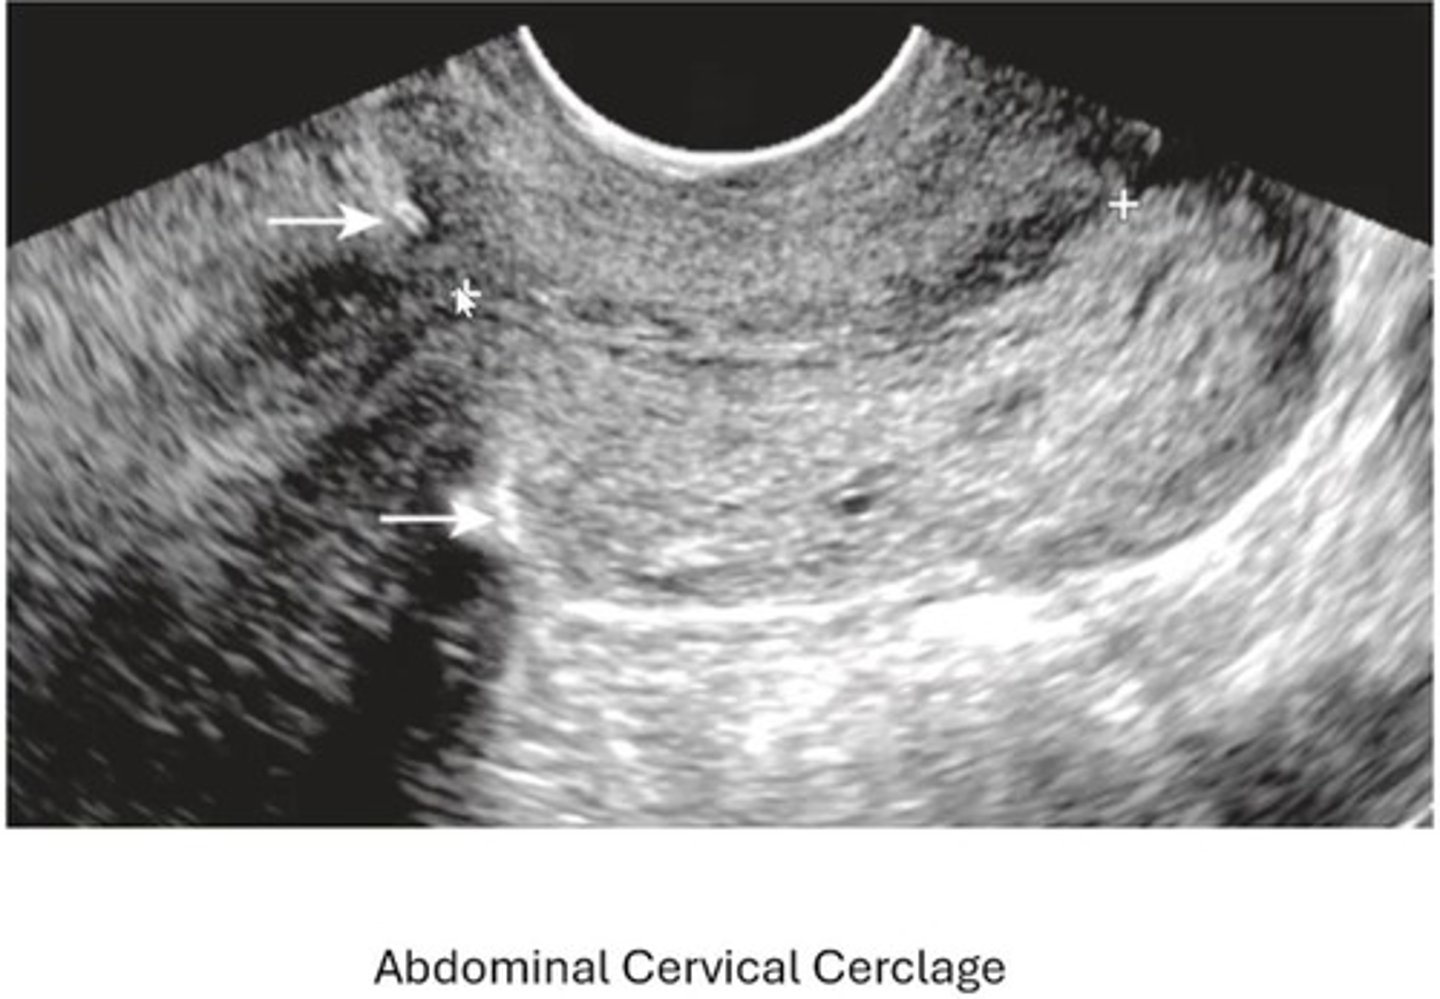

What is a cervical cerclage? When are they inserted?

Suture reinforcing cervical canal integrity inserted at 13-16 wk GA

What is a Mcdonald cerclage?

Purse-string suture around cervix at external os (TV approach)

What is a Shirodkar cerclage?

Suture placed in mid-section of cervix (TV approach)

What is an abdominal suture?

cerclage placed at level of internal os (TA approach)